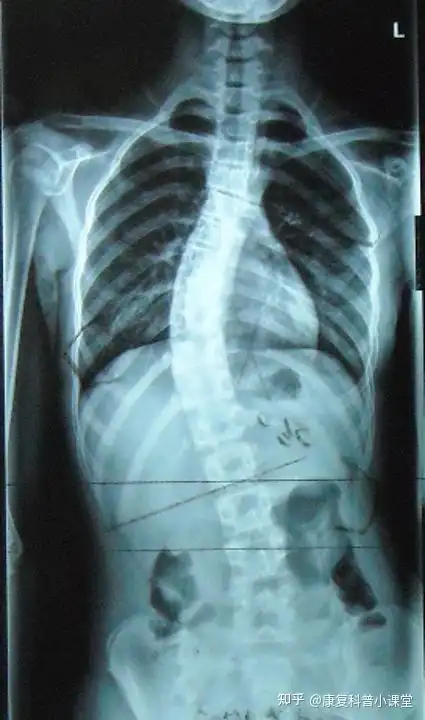

特发性脊柱侧弯的治疗!附手术前后对比照片! - 好大夫在线

后路手术矫形治疗青少年特发性脊柱侧凸畸形(附图片资料) - 好大夫

青少年特发性脊柱侧弯的评估

脊柱侧弯最难矫正曲线病例分享

当他弯腰时你就可以很快发现异常了,由于胸椎侧弯旋转,导致患侧的背部

向左侧的侧弯,人体为了维持平衡就会代偿性的在胸椎产生向右侧的侧弯